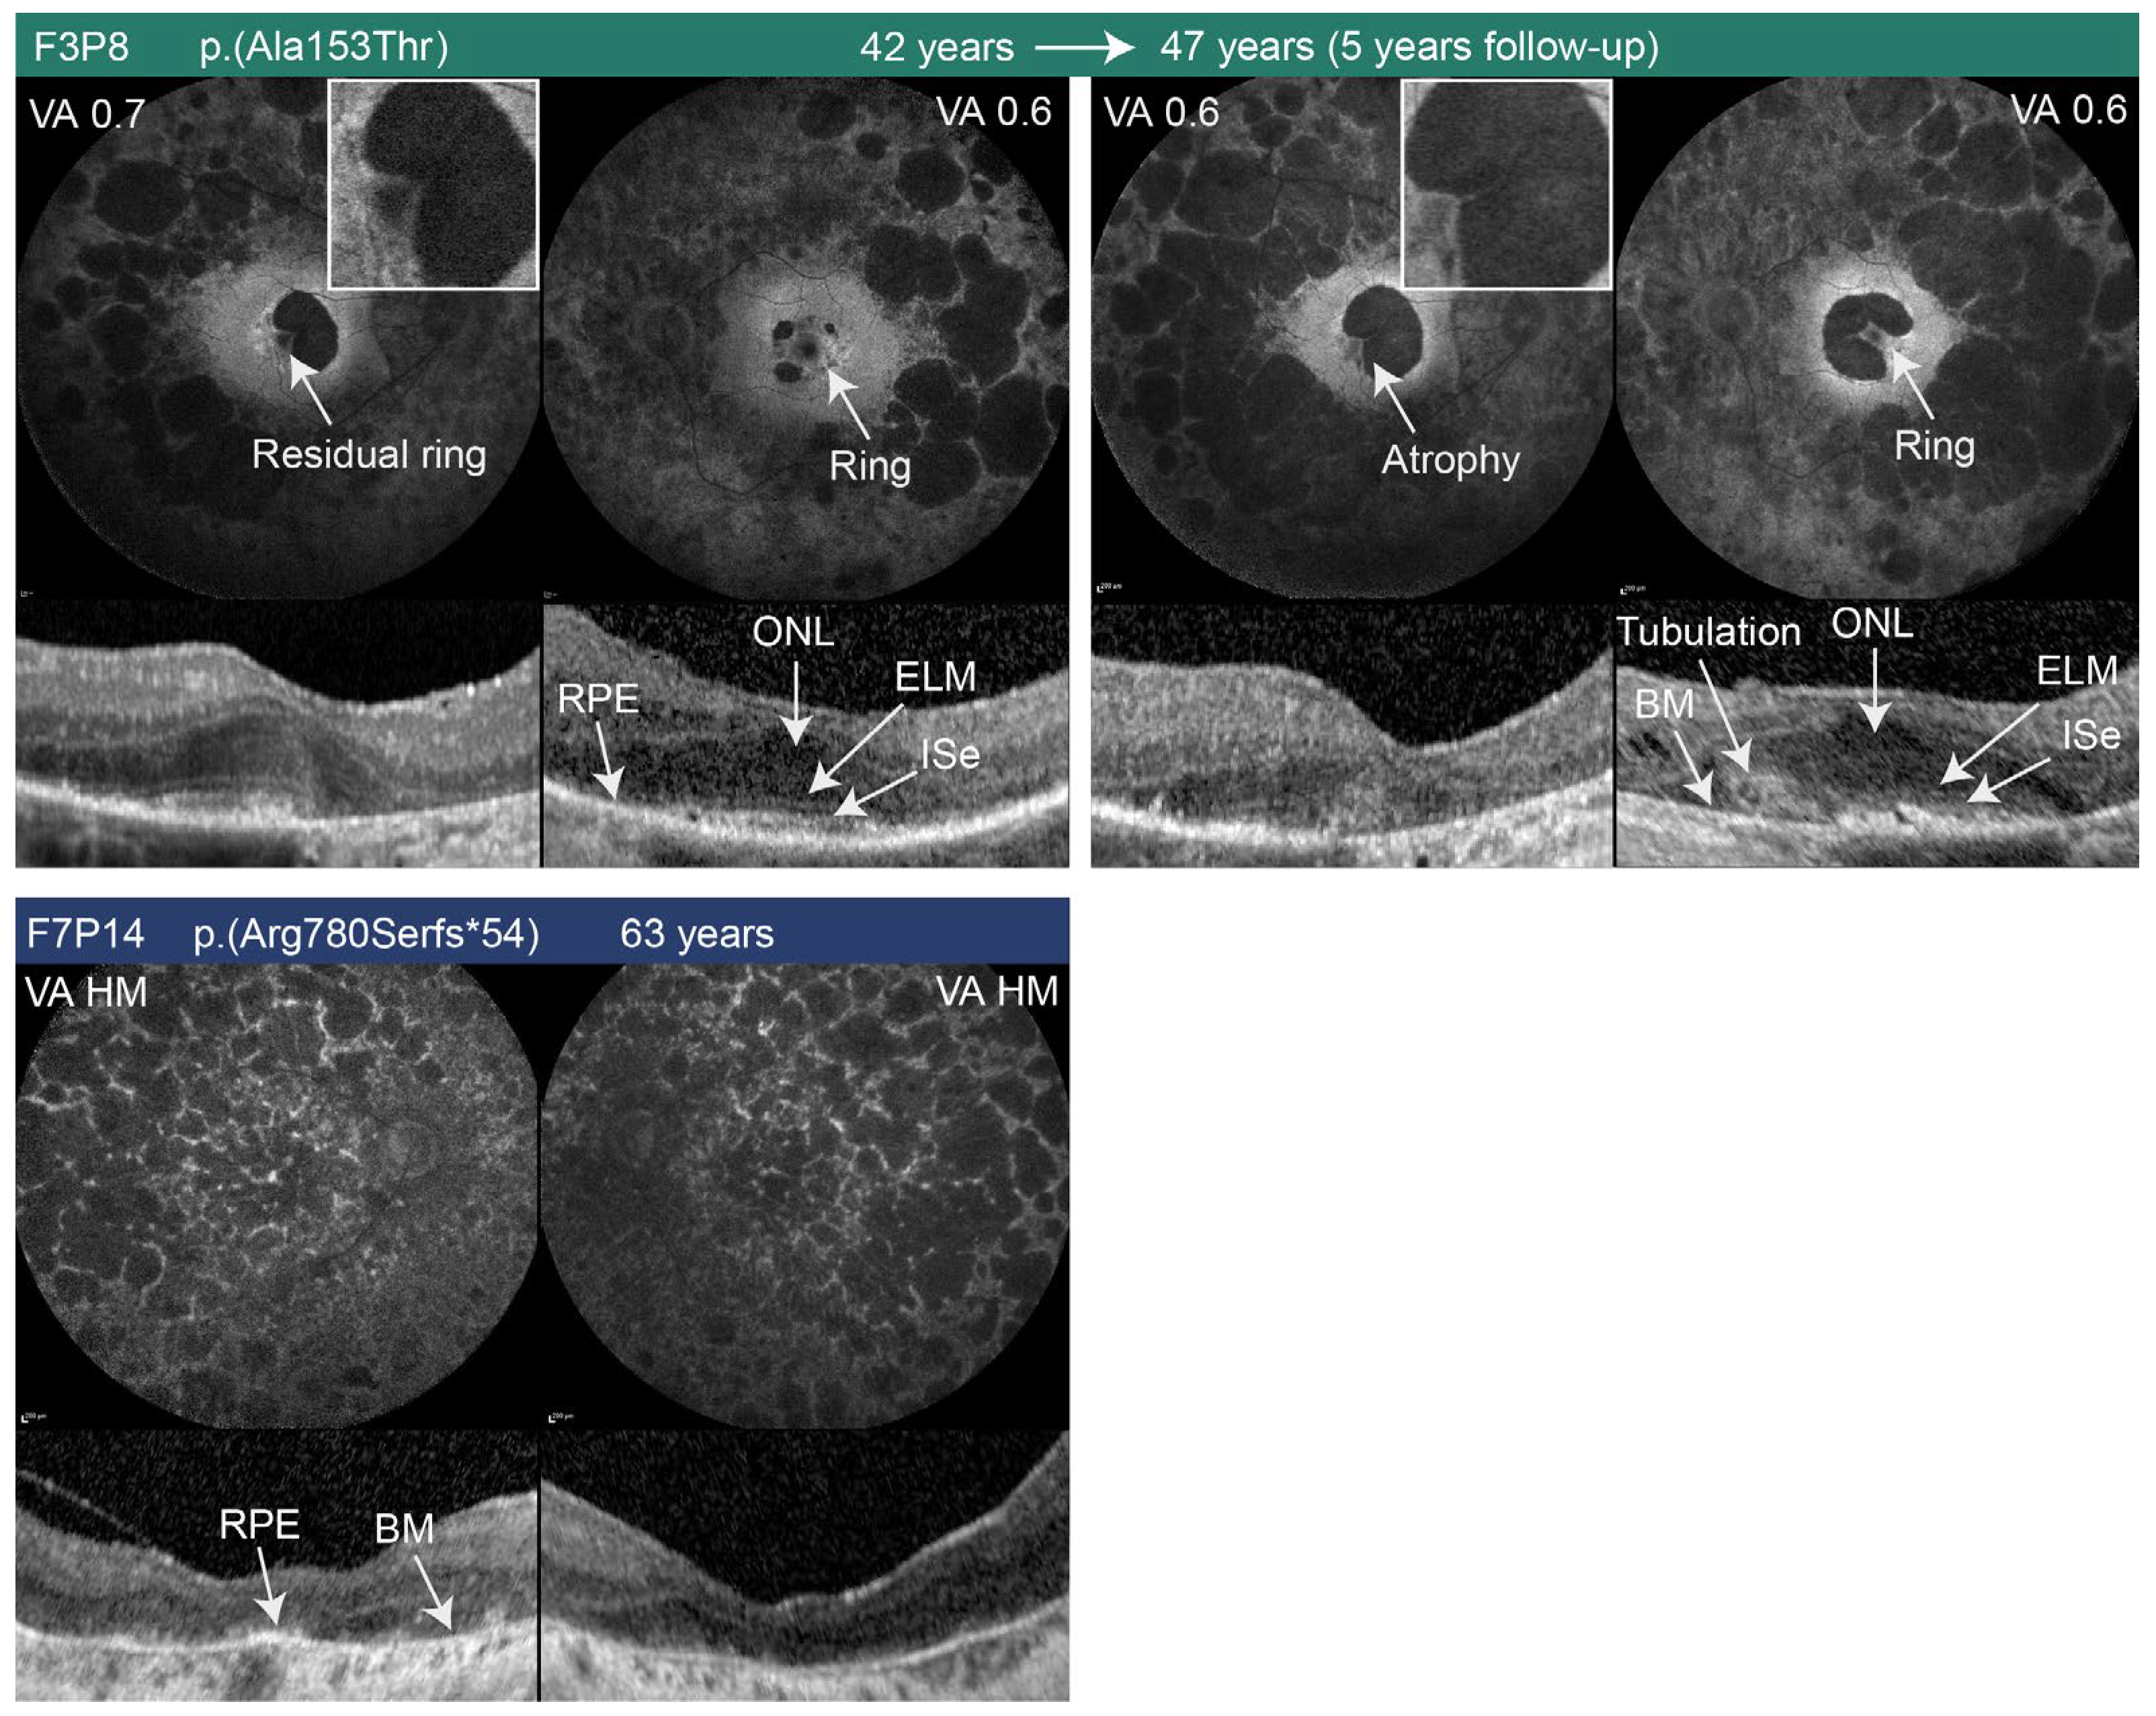

| F3P8 (00419) | M | RP | c.457G>A p.(Ala153Thr) | No | 35; 47 | 35 | N/A (1/15) | −6.5 + 0.25/5° (N/A) | −6.0 + 1.0/90° (N/A) | 0.7 (0.15); 0.6 (0.22) | 0.6 (0.22); 0.6 (0.22) | BE: Constricted central ring; central scotoma | BE: Optic pallor, paramacular atrophy, bone spicules in the peripheral retina | N/A | RE: Absent ELM, Ise, and RPE; LE: remnants of ELM | 85 | 127 | 0.42 (703); 0.28 (408) | 0.19 (507); 0.18 (360) | Was not performed |

| F7P14 (00720) | M | RP | c.2340_2341delAG p.(Arg780Serfs*54) | No | 63 | Childhood | N/A | 0 | 0 | 0.005 (2.30) | 0.005 (2.30) | Could not be performed | BE: Optic pallor, attenuated vessels, chorioretinal atrophy, bone spicules | BE: retinal atrophy | BE: RPE and photoreceptor atrophy, centrally preserved RPE without photoreceptors | N/A | N/A | N/A | N/A | N/A |